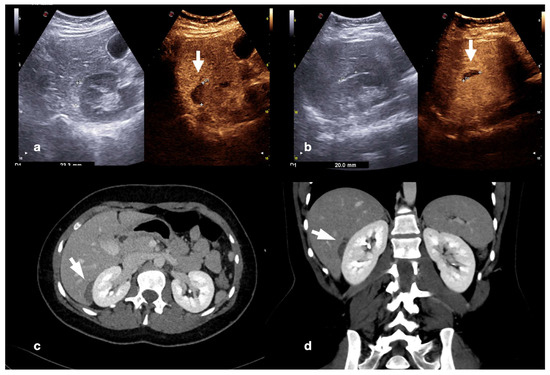

Figure 20.

CEUS (a) of a 23−year-old man referring to the emergency department for direct blunt trauma to the right flank showed the presence of a small pseudoaneurysm (white arrow) inside the contusion area of the right kidney; the diagnosis was then confirmed at the axial arterial phase contrast-enhanced CT scan (b), as well as at angiography performed for treatment purposes (c).